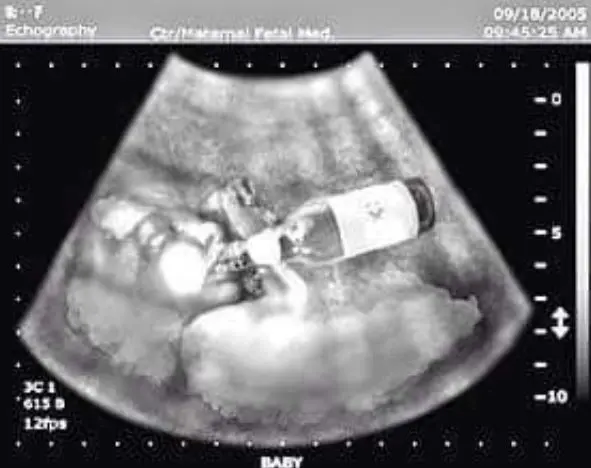

El consumo de alcohol durante el embarazo es un factor de riesgo que puede producir muerte fetal, aborto espontáneo, parto prematuro, retraso del crecimiento intrauterino, y bajo peso al nacer, por este motivo la Sociedad Española de Ginecología y Obstetricia (SEGO) ha insistido en que no existe cantidad de alcohol segura en el embarazo y lo recomendable es dejar de beber antes y durante la gestación.

Uno de los resultados potenciales más incapacitantes de consumir alcohol durante el embarazo es el riesgo de desarrollar el Síndrome Alcohólico Fetal (SAF), la forma clínica más grave y visiblemente identificable del Trastorno del Espectro Alcohólico Fetal (TEAF).